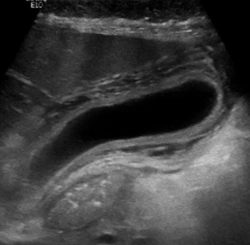

This acute cholecystitis calculator is based on a data-derived risk stratification approach that combines gallbladder ultrasound findings with selected clinical parameters to estimate the probability of acute cholecystitis.[1] It reflects a structured method designed to improve consistency in gallbladder ultrasound interpretation, particularly in cases that do not clearly meet classic diagnostic criteria.

Patel and colleagues describe a framework that addresses a common limitation in radiology reporting. Many gallbladder ultrasound examinations fall into an intermediate category where findings are not definitively positive or negative. This can lead to variability in wording and downstream management recommendations. The proposed model organizes these findings into defined probability categories to support more consistent communication.[1]

The acute cholecystitis risk algorithm proposed by Patel et al [1] synthesizes eleven inputs. Four are non-imaging parameters including age, sex, leukocytosis, and the sonographic Murphy sign. Five are ultrasound-based parameters that characterize gallbladder appearance: gallbladder distention, gallbladder wall assessment, gallbladder contents, presence of a pericholecystic irregular collection, and hepatic artery peak systolic velocity. Two additional inputs allow incorporation of an alternative explanation for symptoms or other imaging findings that substantially increase concern.[1]

A notable feature of this approach is its handling of uncertainty. The sonographic Murphy sign can be positive, negative, or indeterminate. Gallbladder wall thickening is interpreted in context, including distention and possible systemic causes. The model also distinguishes typical sludge from atypical sludge and separates simple pericholecystic fluid from irregular collections that may indicate inflammation. These distinctions align with real-world ultrasound interpretation rather than forcing binary decisions.[1]